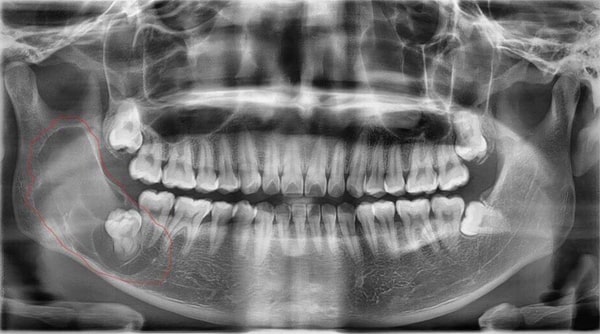

Nhổ răng khôn hay răng số 8 là một quá trình thực hiện bóc tách bác mô nướu, dùng dao chuyên dụng thực hiện mở xương hàm để lấy răng khôn hoặc nhổ nhiều chiếc răng khôn của bạn.

Răng khôn bị nhiễm trùng

Sau khi nhổ răng khôn bị nhiễm trùng là tình trạng huyệt răng bị nhiễm khuẩn do vi khuẩn xâm lấn hoặc vùng nướu và xương hàm bị tổn thương quá nặng gây ra viêm nhiễm và nếu nguy hiểm hơn có thể làm hoại tử.